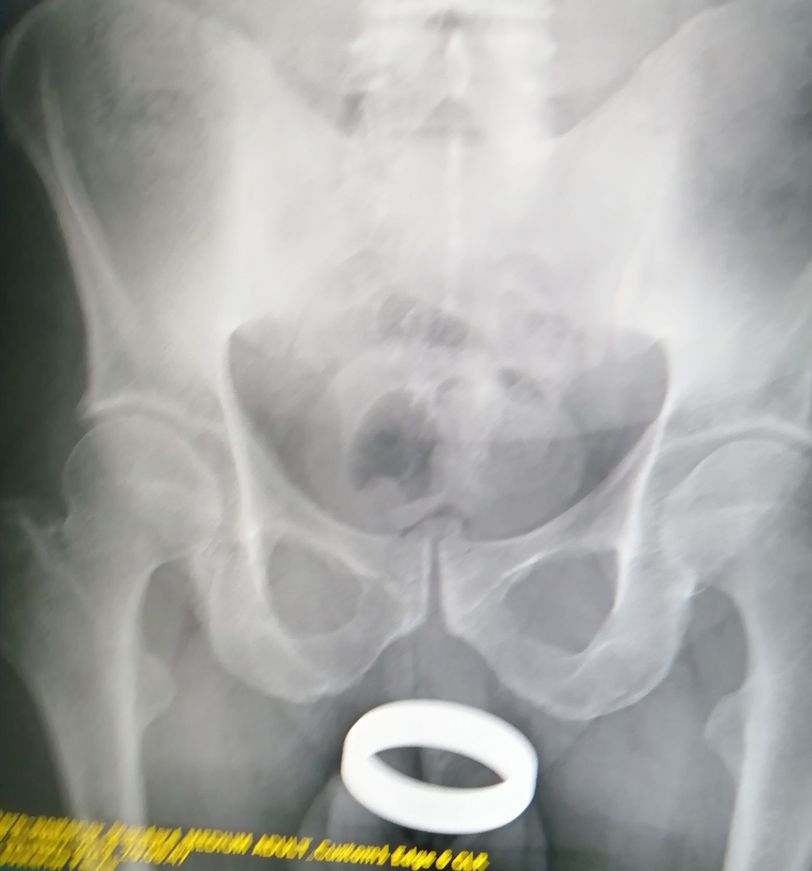

Pelvis AP view

Does anybody have an idea, what it is that thing?

Vaginal pessary ring for prolapse treatment.

I believe it’s a pessary ring used for prolapsed bladder but can be used for other things.